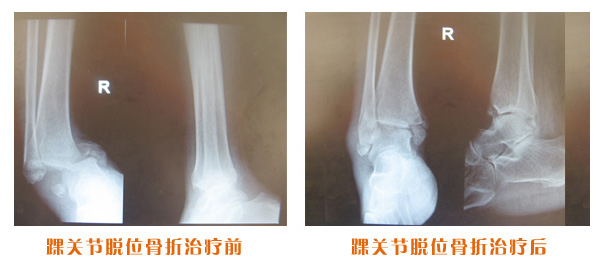

肥城市安駕莊梁氏骨科醫(yī)院是一所以梁氏手法正骨配合膏藥為特色的現代化??漆t(yī)院。

梁氏骨科術始創(chuàng)于清雍正年間,歷經八代,至今已有三百年歷史。據1929年泰安縣志載“梁瑞圖先生,字增生,號蓮峰,安駕莊人,精岐黃并發(fā)明接骨,凡跌打車凡跌打車軋皮不破而碎骨者......【詳細】 |